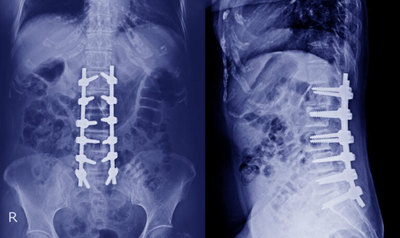

Spine surgery including Endoscopic spine surgery

event-img-1.png

event-img-2.png